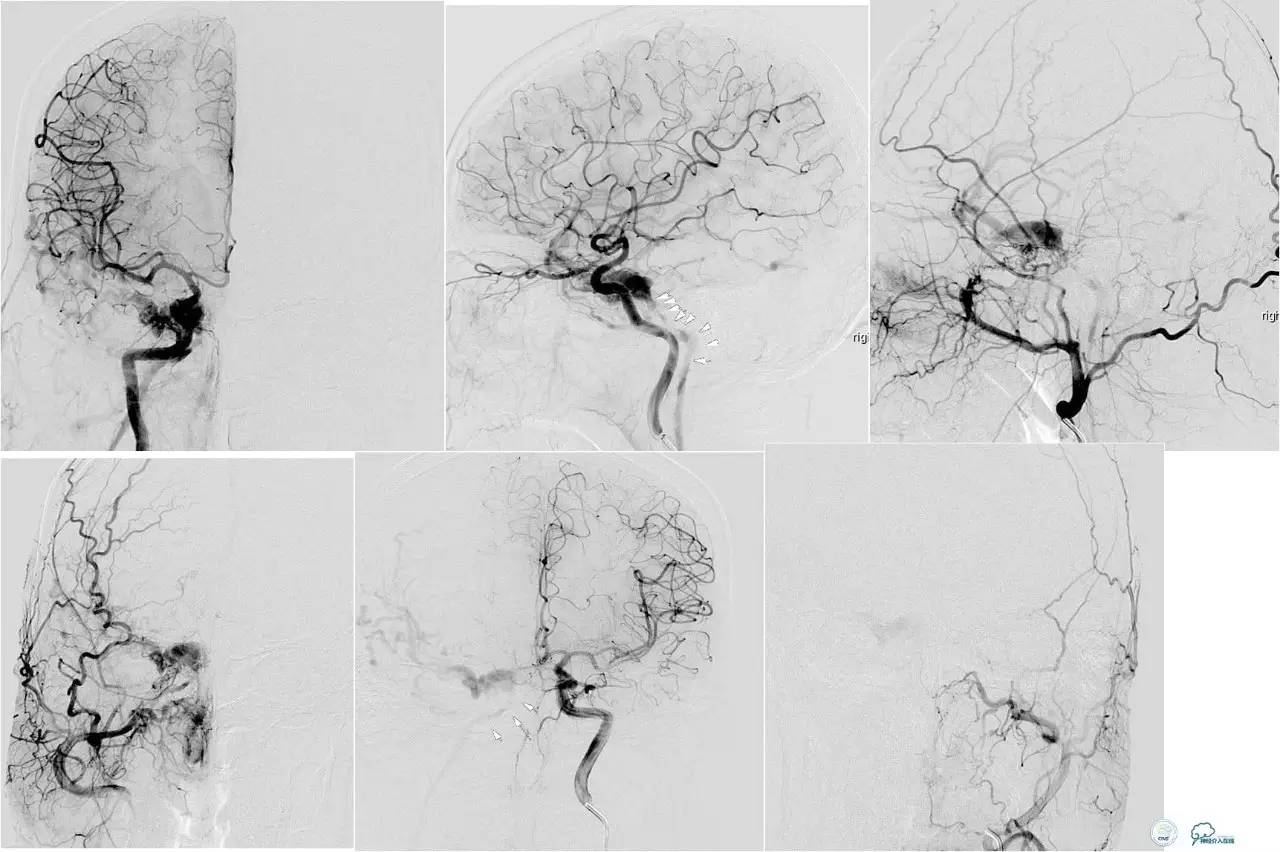

小脑幕缘区DAVF,只有颈外动脉参与供血,供血支细小。

选择抑制血管栓塞,胶无法弥散进入瘘口,选择另一支血管,近端防止Hyperform球囊。

最终胶弥散结果,瘘口完全消失。

小脑幕缘区DAVF,颈外动脉和颈内动脉的供血支均非常细小。

Marathon微导管进入分支后,在主干血管内放置Hyperform球囊。

最终的栓塞结果。

乙状窦区的DAVF,供血动脉细小,静脉引流道通畅。

同侧颈内静脉试图进入引流静脉,但是由于角度问题非常困难。

从对侧颈内静脉绕路进入引流静脉。

Sceptor球囊导管到达静脉内,充盈球囊,让后注入Onyx。

术后造影提示DAVF治愈。